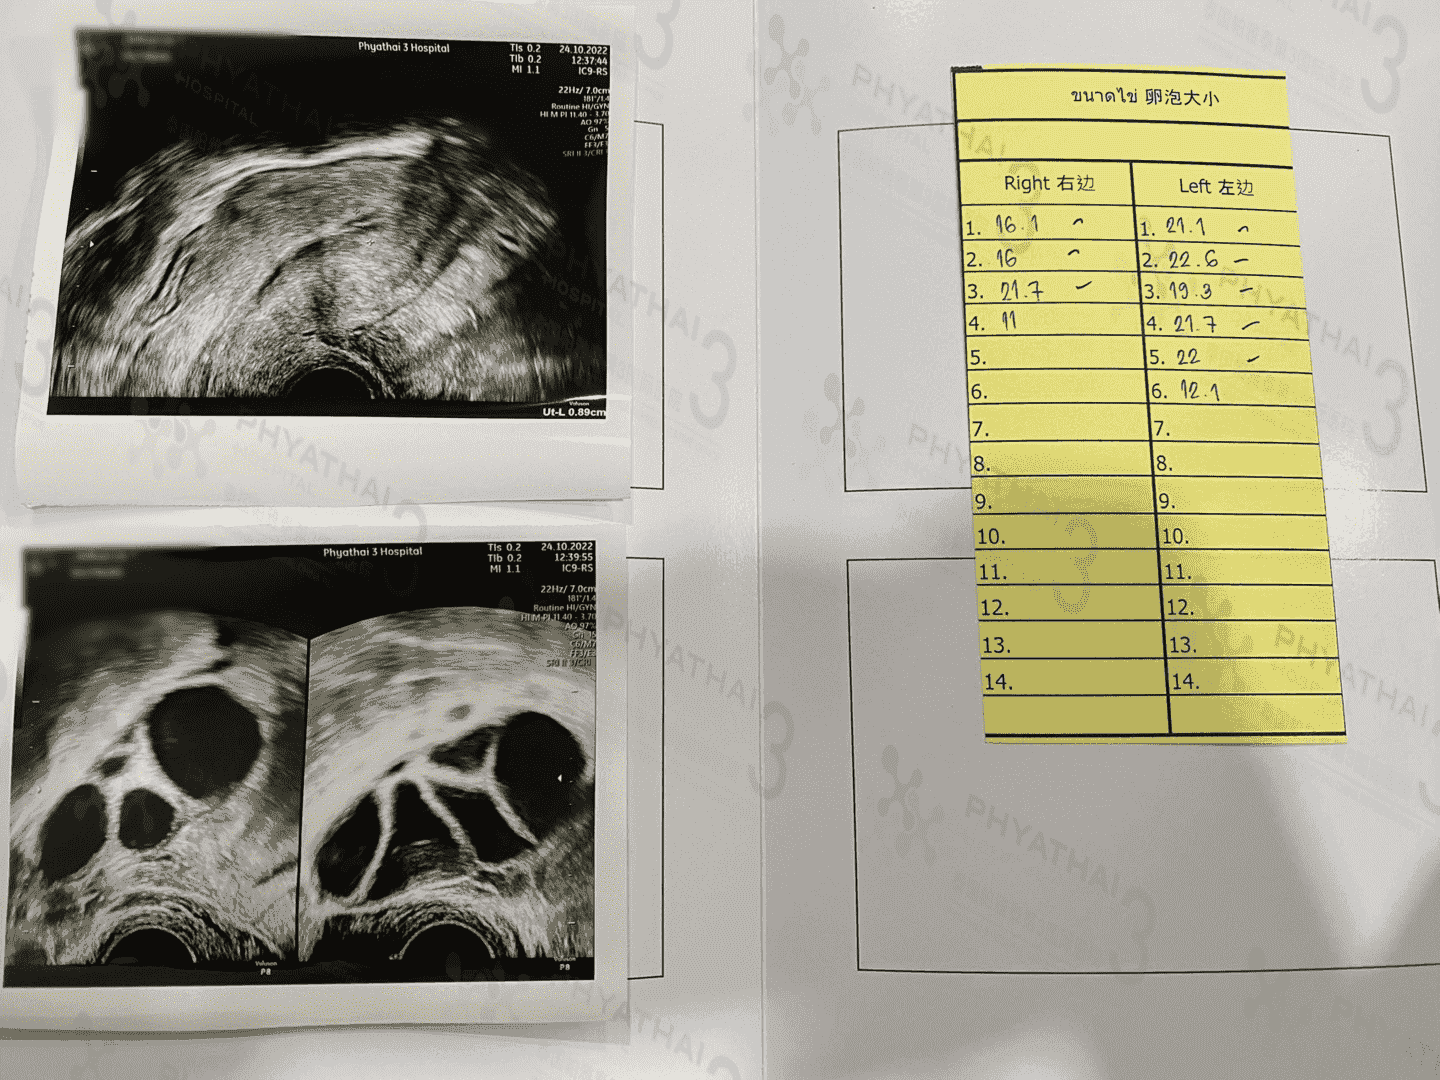

取卵前需要增加饮食营养,保持营养均衡,不要吃辛辣等刺激性食物。饮食以清淡为主。另外,生活一定要规律,避免熬夜等情况的发生。保持心情愉快。取卵过程不是很痛苦,不必担忧,如卵巢位置不佳、卵泡多、怕痛等因素,试管姐妹可以放心麻醉师在静脉打麻醉,注意麻醉前8时禁食水哈。